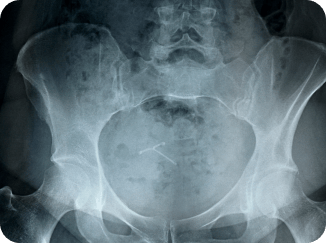

A hip injury is defined as trauma or damage to the hip joint, including fractures, muscle tears, sprains, and impingement. These types of injuries are common among active individuals and the elderly and can be caused by falls, overuse, and muscle or bone degeneration.

The hip joint is the largest joint in the human body, making it often difficult to self-assess the source and reason for the pain. If you’re experiencing a persistent pain in your hip or pain that interferes with your daily life, you should get it assessed by experienced physiotherapists.

The ligamentum teres is a ligament within the hip joint that connects the femoral head (the ball of the thigh bone) to the acetabulum (the hip socket) of the pelvis. This particular ligament can cause hip pain or dysfunction when it tears or suffers an injury after trauma.